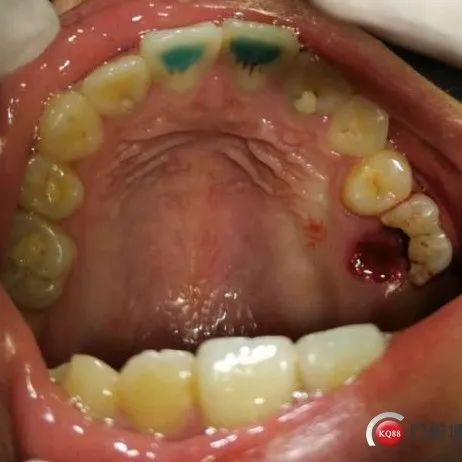

患者女:吴*怡  年龄:17岁主诉:右上后牙破损现病史:右上后曾在我院做了根管治疗既往史:体健,无高血压,心脏病,糖尿病等检查:右上6裂开,腭侧牙冠脱落,探龈下3mm,根尖无明显炎症,牙龈无红肿、瘘管,CT显示髓室底穿孔。右上8牙周状态良好,牙冠完整,根尖无炎症,牙根未发育完成,符合做移植术。和患者家属沟通后同意做移植术,右上8移植到6.患者拍CT后3D打印右上8测量牙冠大小合适。右上8拔除,未拍照6拔牙窝情况。...